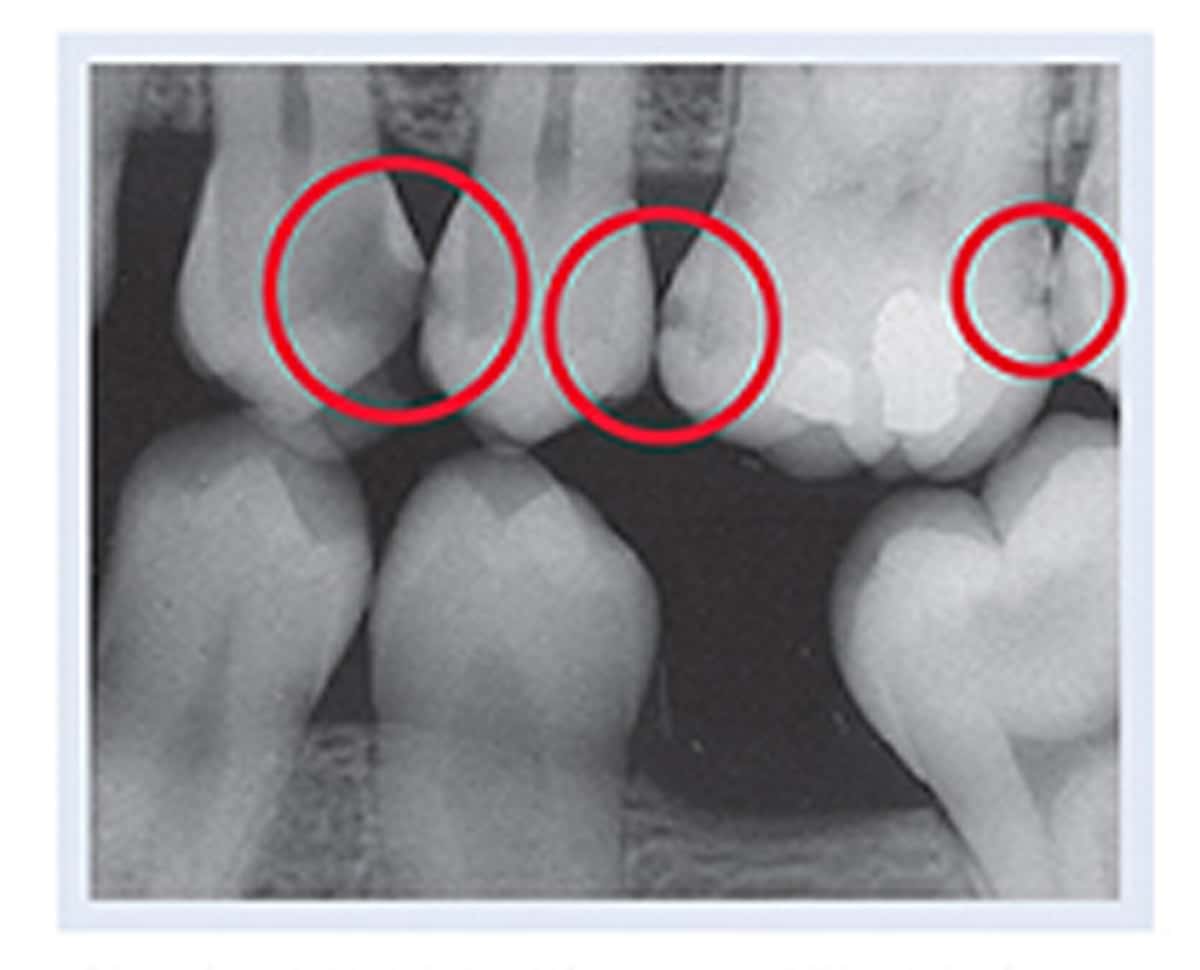

From dentistryfortheentirefamily.com

Dental XRays How to Tell If You Have A Cavity Fridley, MN American Dental Association Xrays It is paramount for dental care practitioners to be aware of the american dental association’s and the us food and drug. Oral health care, including having dental radiographs taken and being given local anesthesia, is safe at any point during pregnancy. They help your dentist look at parts of the mouth that cannot be seen during a regular. 1, 2. American Dental Association Xrays.